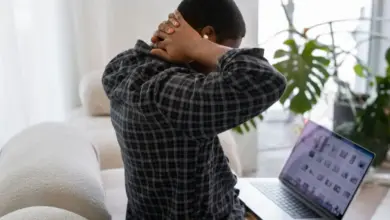

Síndrome da Tensão Cervical: Causas e Tratamentos

A síndrome da tensão cervical geralmente aparece como dor e rigidez no pescoço. A pessoa também pode sentir peso nos…